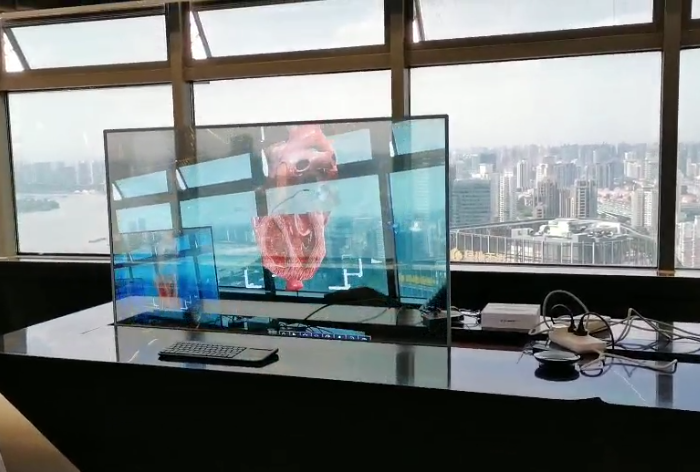

左心耳封堵術流程展示(Watchman)

模擬穿刺、造影、放置等步驟

心臟、血栓房顫展示

空間識別

HoloLens項目體驗:

HoloLens醫療項目截圖: